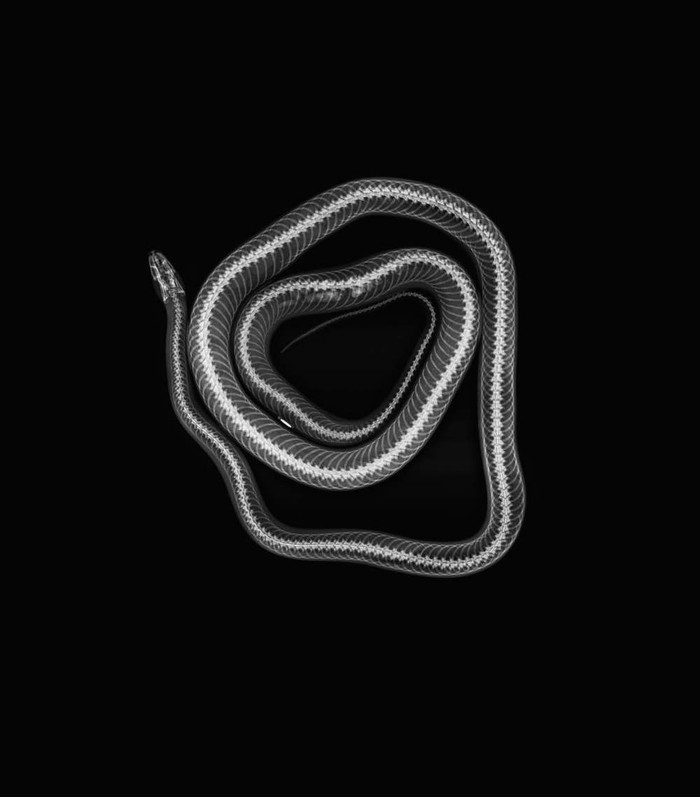

Jakarta - Kebun binatang London dan Oregon merilis foto X-Ray sejumlah hewan-hewannya. Foto tersebut kerap digunakan untuk memantau kondisi kesehatan para hewan.

Deretan Foto X-Ray Para Hewan